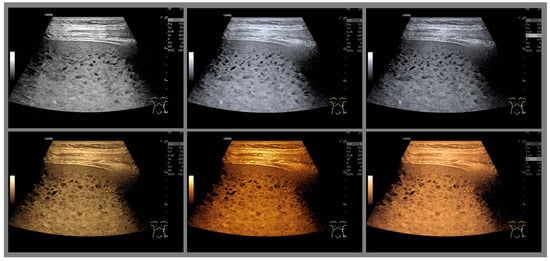

Assessment of Hypertension in Hemodialysis Patients with the Concomitant Use of Peridialytic and Interdialytic Ambulatory Blood Pressure Measurements